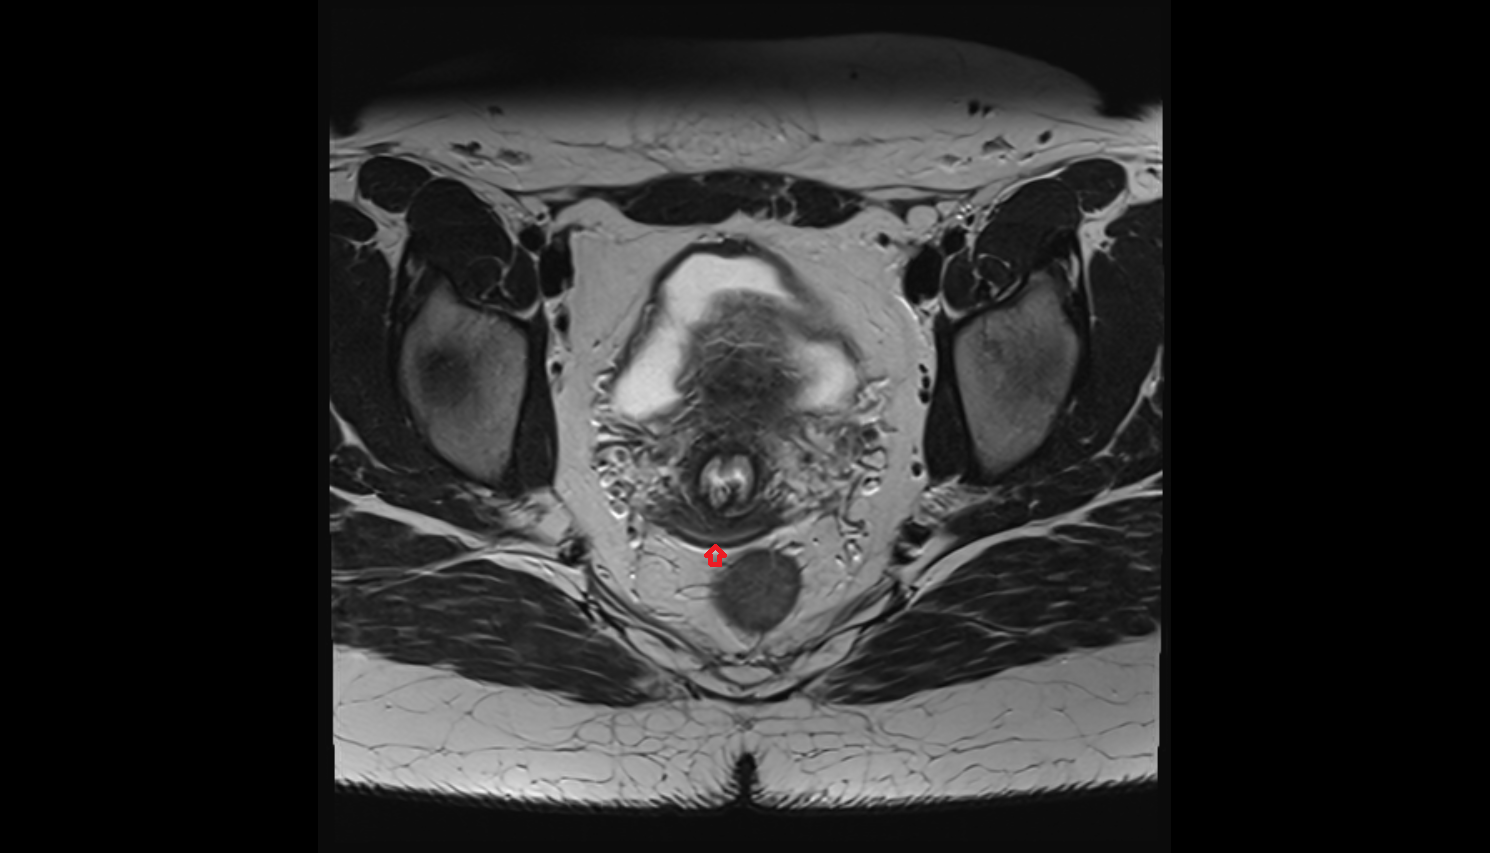

- Rectum

- Urinary bladder

- Uterus

- Body of uterus

- Fundus of uterus

- Cervix of uterus

- Vagina

- Vesicouterine pouch

- Rectouterine pouch (pouch of Douglas)